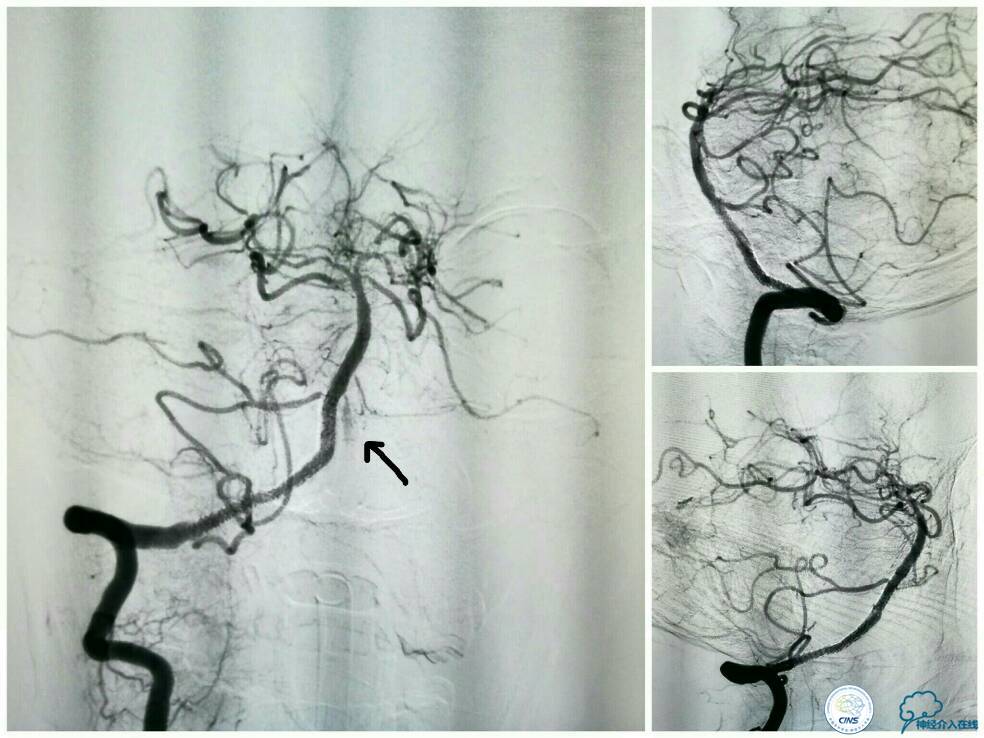

同期行DSA提示右椎动脉V4段发出右PICA后未见顺行显影(图2),左椎动脉V4段-基底动脉汇合处重度狭窄(图3),前循环向后循环的未见明显代偿(图4)。

支架释放过程中给予替罗非班3 ml/h静脉持续泵入,以预防急性血栓形成。最后一枚支架释放完毕后造影显示右椎动脉V4段再通,支架贴壁良好,前向血流TICI分级3级,左椎动脉V4段逆向显影(箭头)(图11)。